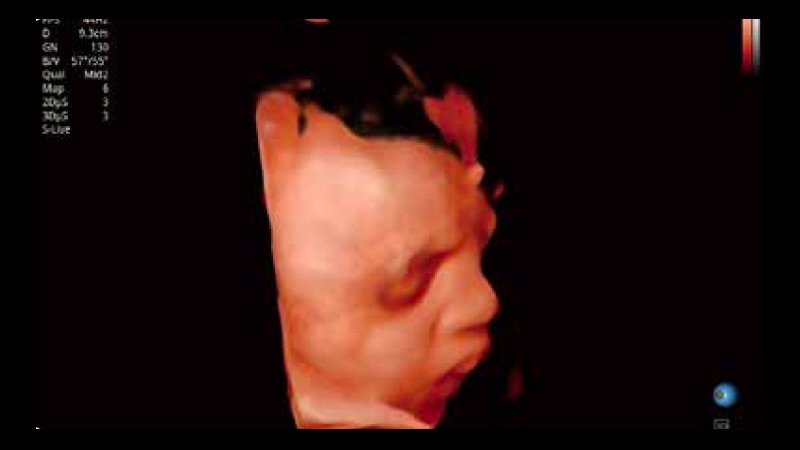

開立醫(yī)療通過不斷的技術(shù)創(chuàng)新,為大眾的生命健康提供持續(xù)關(guān)愛。P12 Plus采用全新一代超聲成像平臺(tái),新平臺(tái)旨在將真實(shí)還原組織解剖結(jié)構(gòu)作為首要目標(biāo)。平臺(tái)采用全新集成化硬件模塊,搭載新一代芯片,系統(tǒng)性能得到大幅提升,為您的診斷提供了豐富的臨床信息。優(yōu)異的圖像表現(xiàn),豐富的探頭配置,全面的應(yīng)用功能,為您日常診斷提供了可靠的助手。

P12 Plus

彩色多普勒超聲診斷系統(tǒng)